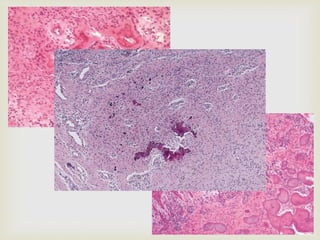

 Well- circumscribed: especially when the

proliferation occurs within the perineurium of the

involved nerve

 Tumours that proliferate outside the perineurium

blend with the adjacent connective tissue

 Tumour is composed of

 Interlacing bundles of spindle shaped cells

 Cells often exhibit wavy nuclei

 Delicate collagen bundles

 Myxoid matrix

 Sparsely distributed small axons are present within the

lesional tissue : demonstrated by silver stains